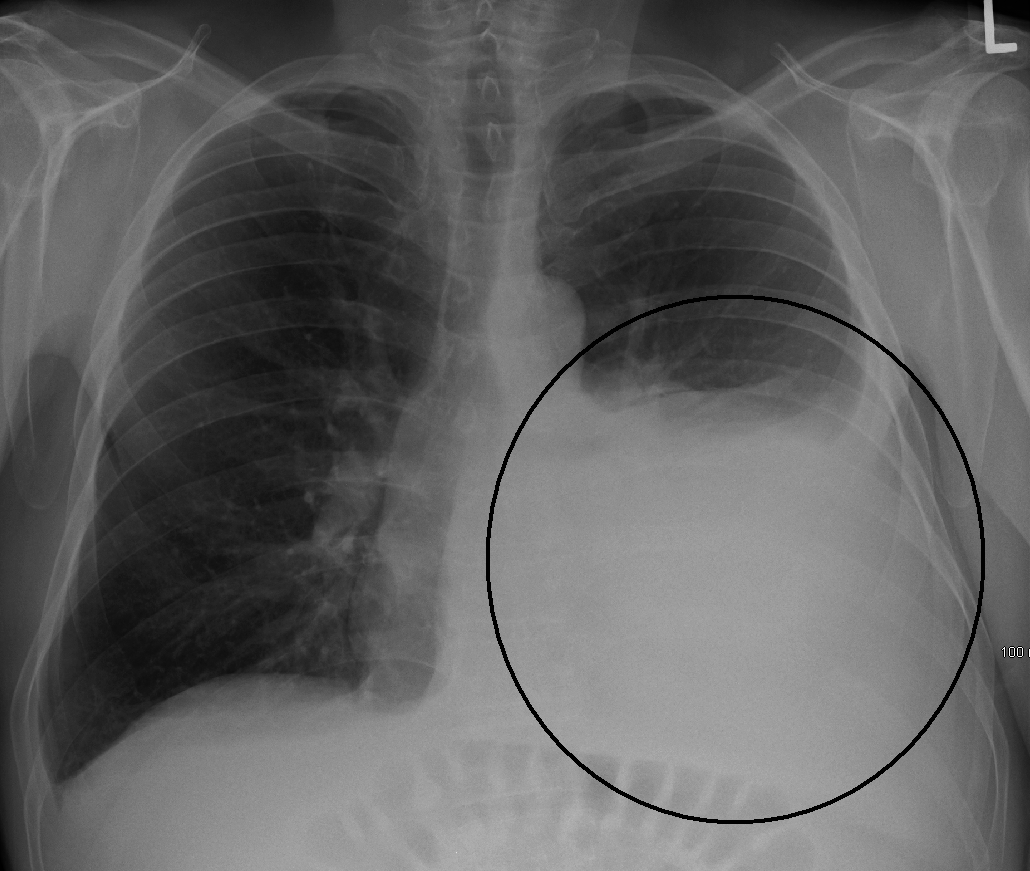

¿En qué escenarios clínicos se ven disminuídas las vibraciones vocales en la palpación? Afonía Disfonía Enfisema Derrame pleural